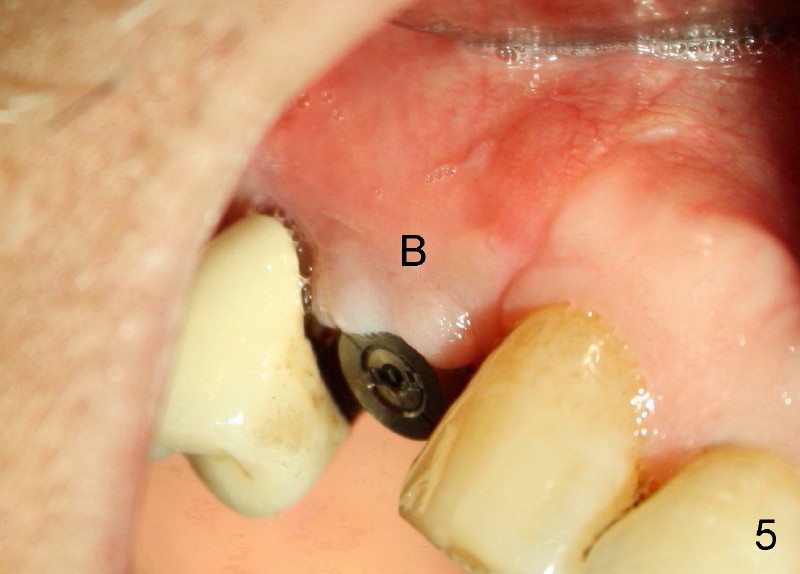

Sixty-eight year old healthy man has had multiple implants.  He readily accepted immediate implant when the tooth #5 had subgingival fracture of the lingual cusp (Fig.1).  A 5x20 mm Tatum screw implant was placed immediately after atraumatic extraction and bone expansion (Fig.2 I).  Implant rough surface was exposed buccally and lingually when the implant was placed equigingivally proximally.  Two buccal accessory incisions were made.  The flap was raised with scoring the periosteum underneath, advanced downward (as shown in Fig.3 arrow) and sutured to the lingual papilla.  The buccal aspect of the implant is covered, whereas the lingual rough surface remains partially exposed (Fig.4 arrow), assuming that the palatal mucoperiosteum is tough to advance even with release incisions.

Fig.3 and 4 are taken 1 week postop, whereas Fig.5 and 6 (mirror view) are taken 2 weeks postop.